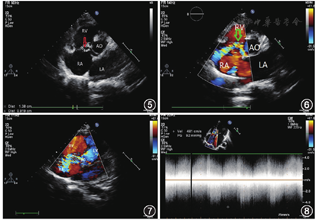

例1患者,男,26岁,因"活动后心悸、乏力1个月,咳嗽、咳痰1周"入院。体格检查:胸骨左缘4~5肋间可闻及3/6级收缩期喷射样杂音。胸超声心动图显示:主动脉瓣下、三尖瓣隔瓣上方间隔回声中断约12 mm,该处可探及左向右分流血流信号,最高血流速度(peak vilocity, VP)4.56 m/s,右心房内可见一直径约28 mm的囊袋样结构,略呈半圆形,与上述间隔中断处相通,该囊袋样结构随心脏舒缩轻微活动,其上可见约10 mm的回声中断,该处可探及流向右心室的双期连续性分流血流信号,VP 7.75 m/s。诊断提示:考虑左心室右心房通道伴室间隔膜部瘤形成(图1,图2,图3,图4)。术中经食道超声提示:主动脉窦瘤破入右心房,主动脉右冠窦可见呈囊袋状向右房突出,上方紧邻三尖瓣隔瓣、下方紧邻主动脉右冠瓣,囊袋基底宽约21 mm,深约23 mm,囊袋上可见一破口,此处可探及连续性血流频谱,VP 2.81 m/s,压差(pressure gradient,PG)32 mmHg (1 mmHg= 0.133 kPa)。术中见三尖瓣隔瓣上一主动脉窦瘤,大小约3 cm × 2 cm,剪开窦瘤,基底部缺损约1.5 cm × 1.5 cm,修补缺损窦壁。患者术后恢复良好,顺利出院。误诊分析:左心室右心房通道又称为Gerbode缺损,目前认为是一种特殊的膜周部室间隔缺损,由于三尖瓣瓣叶阻挡或右心室纤维素形成,使左心室分流的血液直接进入右心房内;常位于膜部室间隔三尖瓣瓣环旁,一般可探及左心室血流向右心房分流。本例患者病变发生在三尖瓣隔瓣附近,可探及左向右的异常血流信号,多普勒超声并非典型的双期血流频谱,且主动脉窦部无明显增宽,故考虑诊断为左心室右心房通道;右心房可查见囊袋样结构随心脏舒缩轻微活动,且在顶部可见回声中断,并在此处探及流向右心室的血流束,超声图像与室间隔膜部瘤破裂特点相似,故有误诊可能。